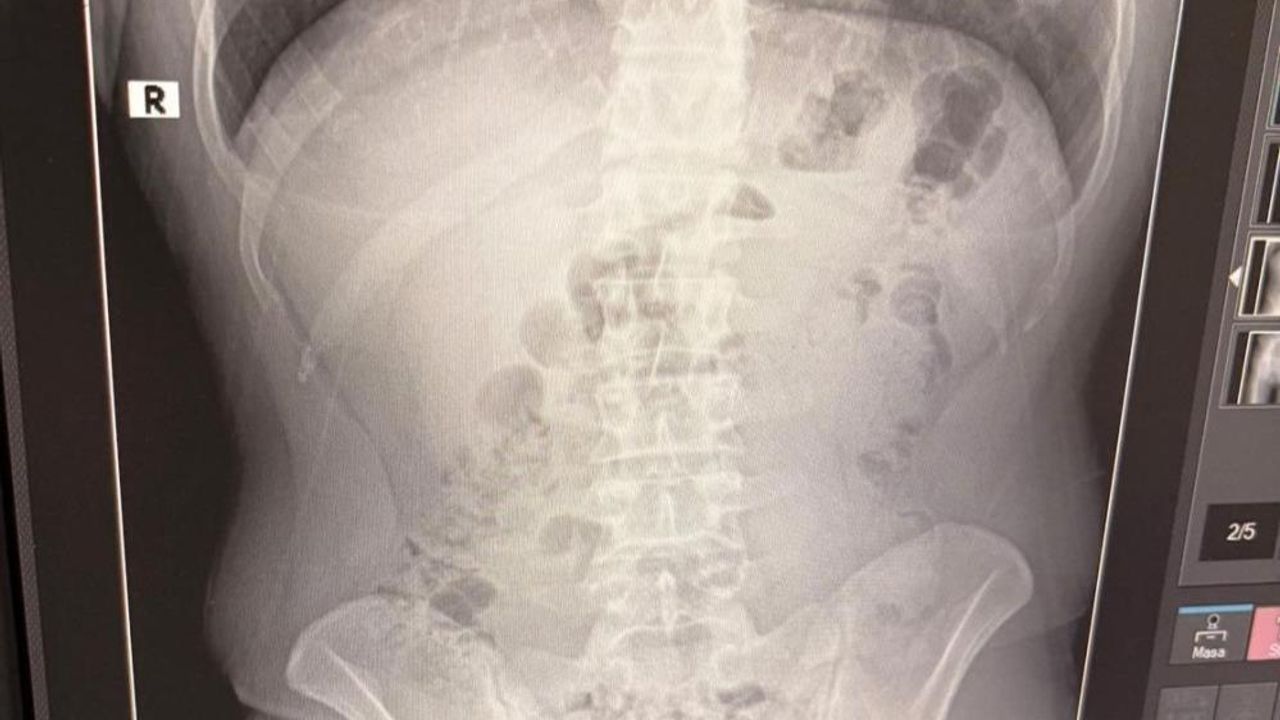

Adreste yapılan arama sırasında ekipler, şüphelilerden birinin üstünde 1 adet kapsül ele geçirdi. Şüphe üzerine tüm şüpheliler hastaneye götürüldü ve yapılan röntgen kontrollerinde 3 kişinin midelerinde kapsül içine gizlenmiş metamfetamin tespit edildi.

Hastanede tedavi altına alınan şüphelilerin vücudundan kapsüller çıkarılırken, adreste ele geçirilenlerle birlikte toplam 1 kilo 516 gram metamfetamin ele geçirildi.